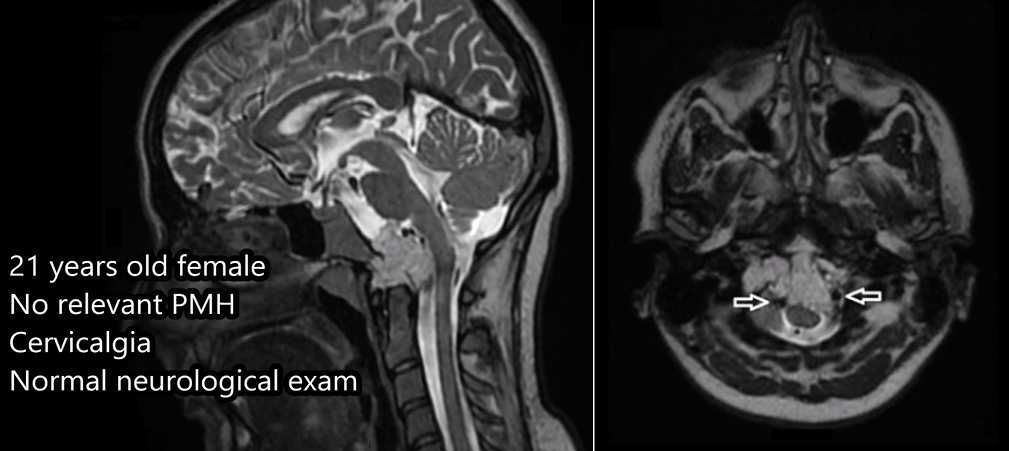

颅颈交界区脊索瘤是“国际疑难”手术之一,特别是当肿瘤侵犯到硬膜内和脑组织、神经血管黏连时。21岁女孩,因颈部疼痛做MRI检查发现脊索瘤,在颅颈交界区、枕骨大孔内呈侵袭性生长,累及双侧椎动脉,硬膜内侵犯,手术风险较大,曾一度治疗无望。

术前MRI